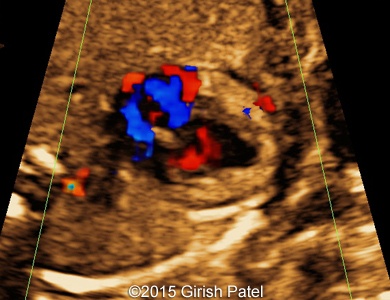

Following images and videos show a case of double inlet left ventricle with transposition of the great arteries that was seen at 26 and 36 weeks of otherwise non-complicated pregnancy.

Images 1, 2, 3, and 4: 2D images showing transverse scan of the heart with double inlet left ventricle and transposition of the great arteries. Following structures can be seen: dominant enlarged left ventricle (LV); diminutive right ventricle (RV) connected to the left ventricle via small bulboventricular foramen; both, left atrium (LA), and right atrium (RA) open to the left ventricle via separate tricuspid and mitral valves; foramen ovale flap can be seen within the left atrium; enlarged pulmonary artery (PA) arises from the left ventricle; small part of the aorta (Ao) arising from the diminutive right ventricle can be also seen.

Images 5, 6, 7: 2D color Doppler images showing the heart with double inlet left ventricle and transposition of the great arteries. Image 5 shows filling of the left ventricle via separate mitral and tricuspid valves (doubled red flow). Images 6 and 7 shows parallel arrangement of the aorta and pulmonary artery (blue flows).